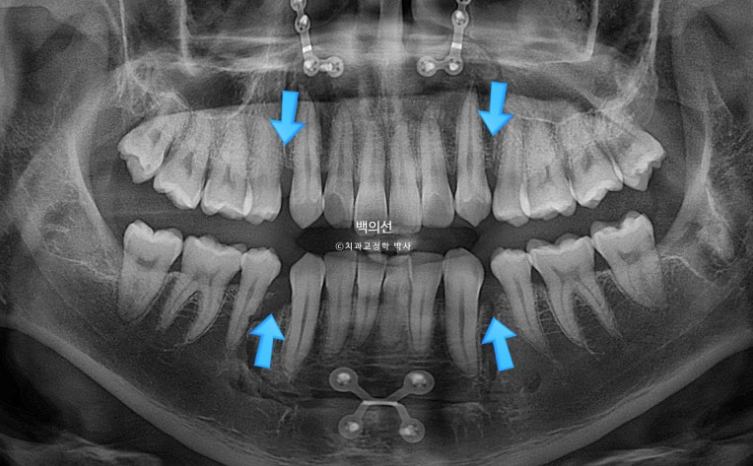

치근흡수는 없으며 치근평행도는 좋습니다.

이제 전 후 비교 보겠습니다.

24.10~25.08

앞니가 깊게 물리는 과개교합도 좋아졌습니다.